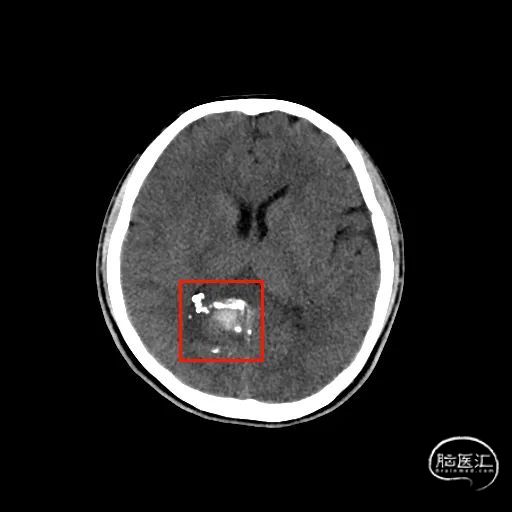

图1. 头部CT及CTA提示:右侧半卵圆区-侧脑室旁血肿,右侧血肿旁局部小动脉血管稍增粗,血管畸形待排。

图4. 术后CT复查未见新发出血。